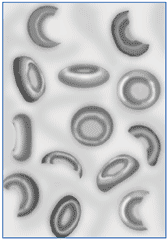

| Glóbulos vermelhos danificados (esquistocitos). | |